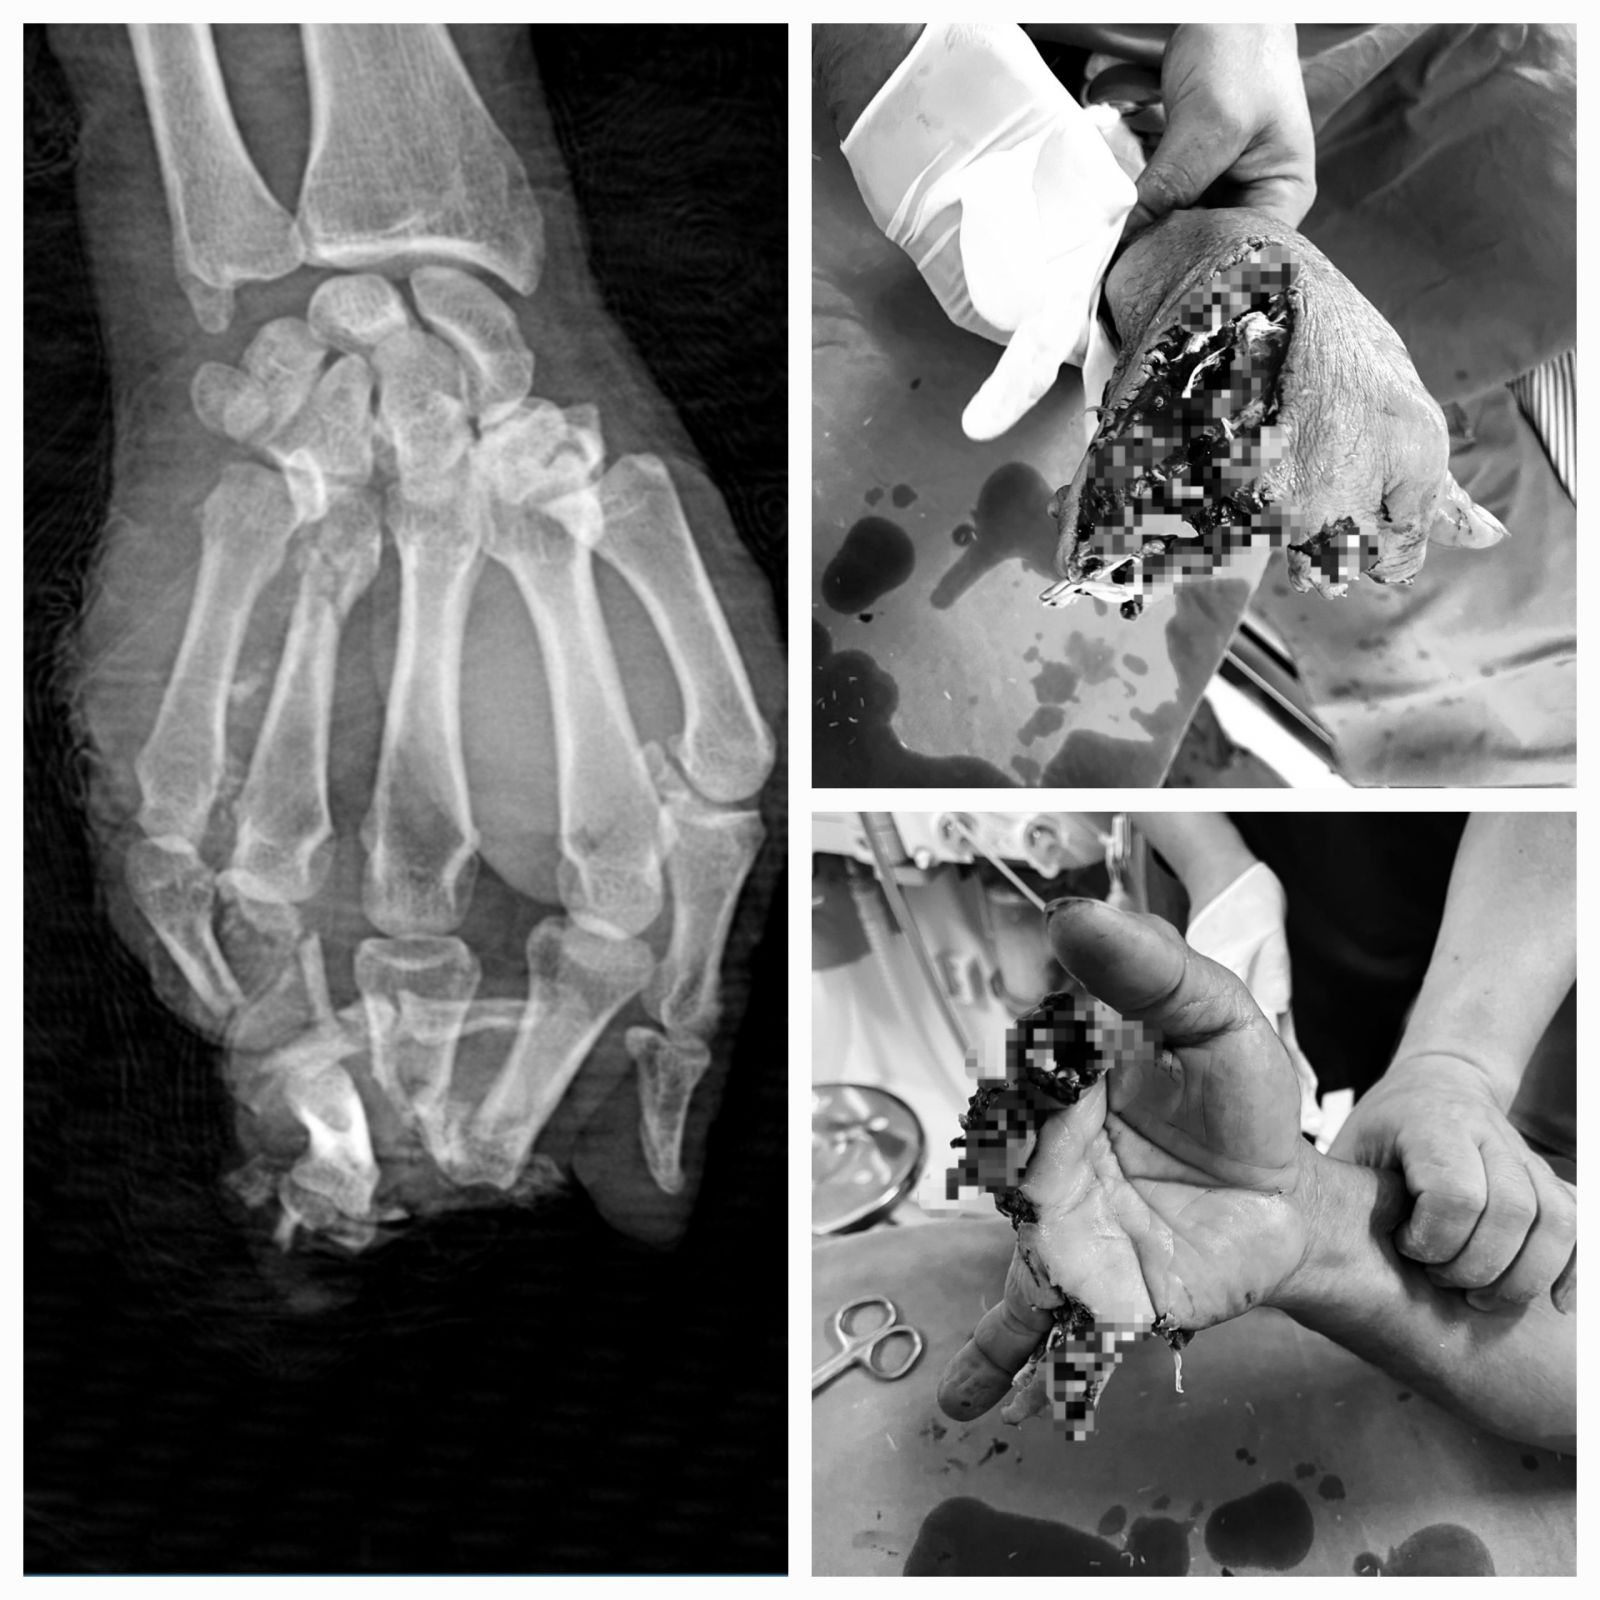

Hình ảnh vết thương của BN sau tai nạn LĐ

Nam bệnh nhân (ở xã Phúc Sơn, huyện Lâm Bình) bị máy bào cắt vào bàn tay phải. Được người nhà đưa đến TTYT huyện Chiêm Hóa trong tình trạng ngón 2, 3,4,5 bàn tay phải vết thương dập nát hoàn toàn, mất ngón, khuyết da che phủ phần mềm, chảy máu.

Bệnh nhân nhanh chóng được cầm máu, cố định vết thương và chuyển phẫu thuật ngay sau đó. Theo đó, các Bác sĩ đã tiến hành cắt lọc bơm rửa lấy hết dị vật trong vết thương, cắt lọc tổ chức dập nát làm sạch vết thương, tạo mỏm cụt các đầu chi, cắt lọc bảo tồn gân, cố định xương gãy ở tư thế chức năng, khâu nối lại hệ thống gân bị đứt…